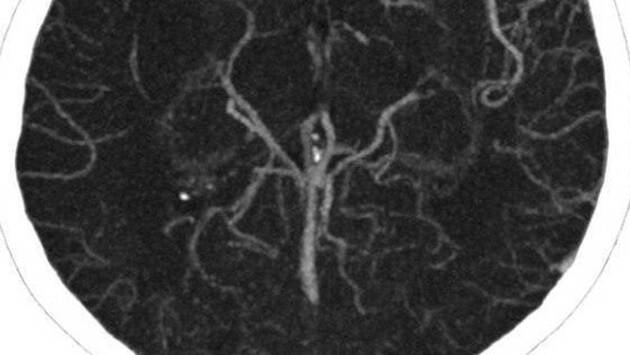

«В Мытищинскую больницу поступил 70-летний мужчина с жалобами на сильные боли в ноге, хромоту и почерневший палец на стопе. Проведенное обследование установило значительное поражение артерий нижних конечностей и начавшийся некроз пальца. Также оказалось, что у пациента критическое сужение сонных артерий – около 15 см от ключицы до основания черепа. Такое состояние развилось на фоне прогрессирующего атеросклероза», – говорится в сообщении.

В ведомстве отметили, что врачам предстояло бороться не только за спасение ноги пациента от ампутации, но и за его жизнь, так как множественные сужения на разных участках сонной артерии достигали 70–90%.

«Стенки сосудов были не эластичными, как должно быть в норме, а хрупкими из-за отложений кальция. По плотности они напоминали хрусталь. Был крайне высок риск инсульта. Понадобилась срочная операция по удалению атеросклеротических бляшек в сосудах. Она заняла около трех часов и прошла успешно. <...> После заживления операционного разреза провели плановую операцию по реконструкции артерий нижней конечности и компенсировали в ней кровообращение, болевой синдром купирован», – приводит пресс-служба слова заведующего отделением сосудистой хирургии Родиона Шилова.